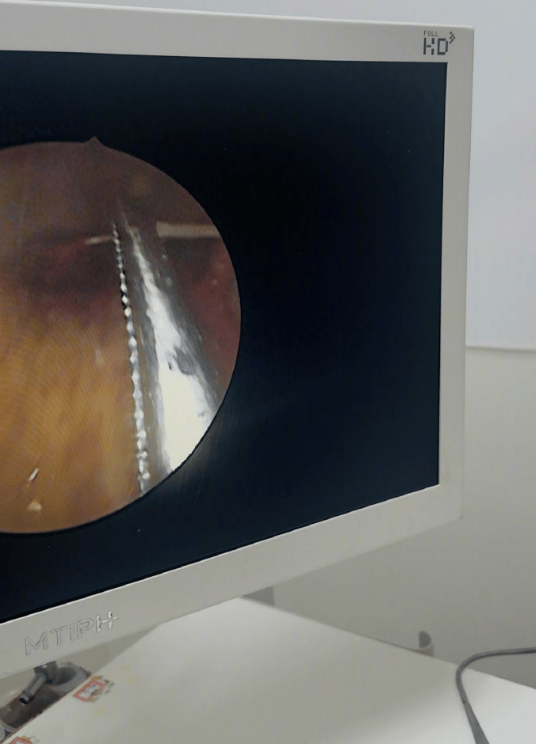

搜狐娱乐讯 6月1日,柳岩发文称自己因为吃鱼的时候,卡到鱼刺去医院的经历,在医生的专业帮助之下,很快就“解脱”了,现在已经没有事。柳岩还在线提醒大家,遇到相似情况一定要及时就医!

之后柳岩还在评论区与网友互动,称自己并没有划伤食道,目前没有什么事。